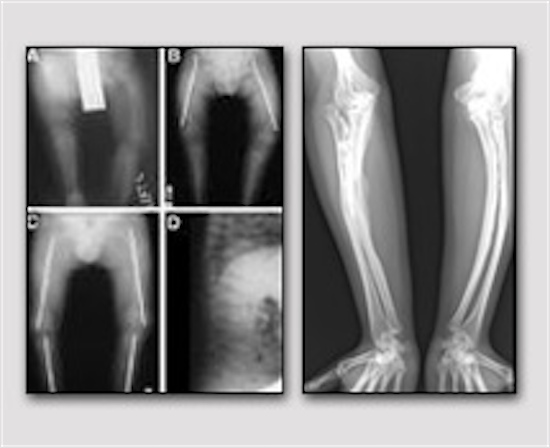

L’Osteogenesi Imperfetta interessa 1 su 10.000 nati. Le fratture spontanee rappresentano il tratto distintivo dell’Osteogenesi Imperfetta, e determinano, soprattutto durante l’infanzia, la necessità di interventi chirurgici, anche frequenti.

Le deformità dell’apparato scheletrico completano il quadro di sintomi causati dalle anomalie del tessuto connettivo osseo all’origine della malattia e contribuiscono a causare handicap fisici, anche gravi, che rendono complessa l’autonomia della persona che ne è affetta.